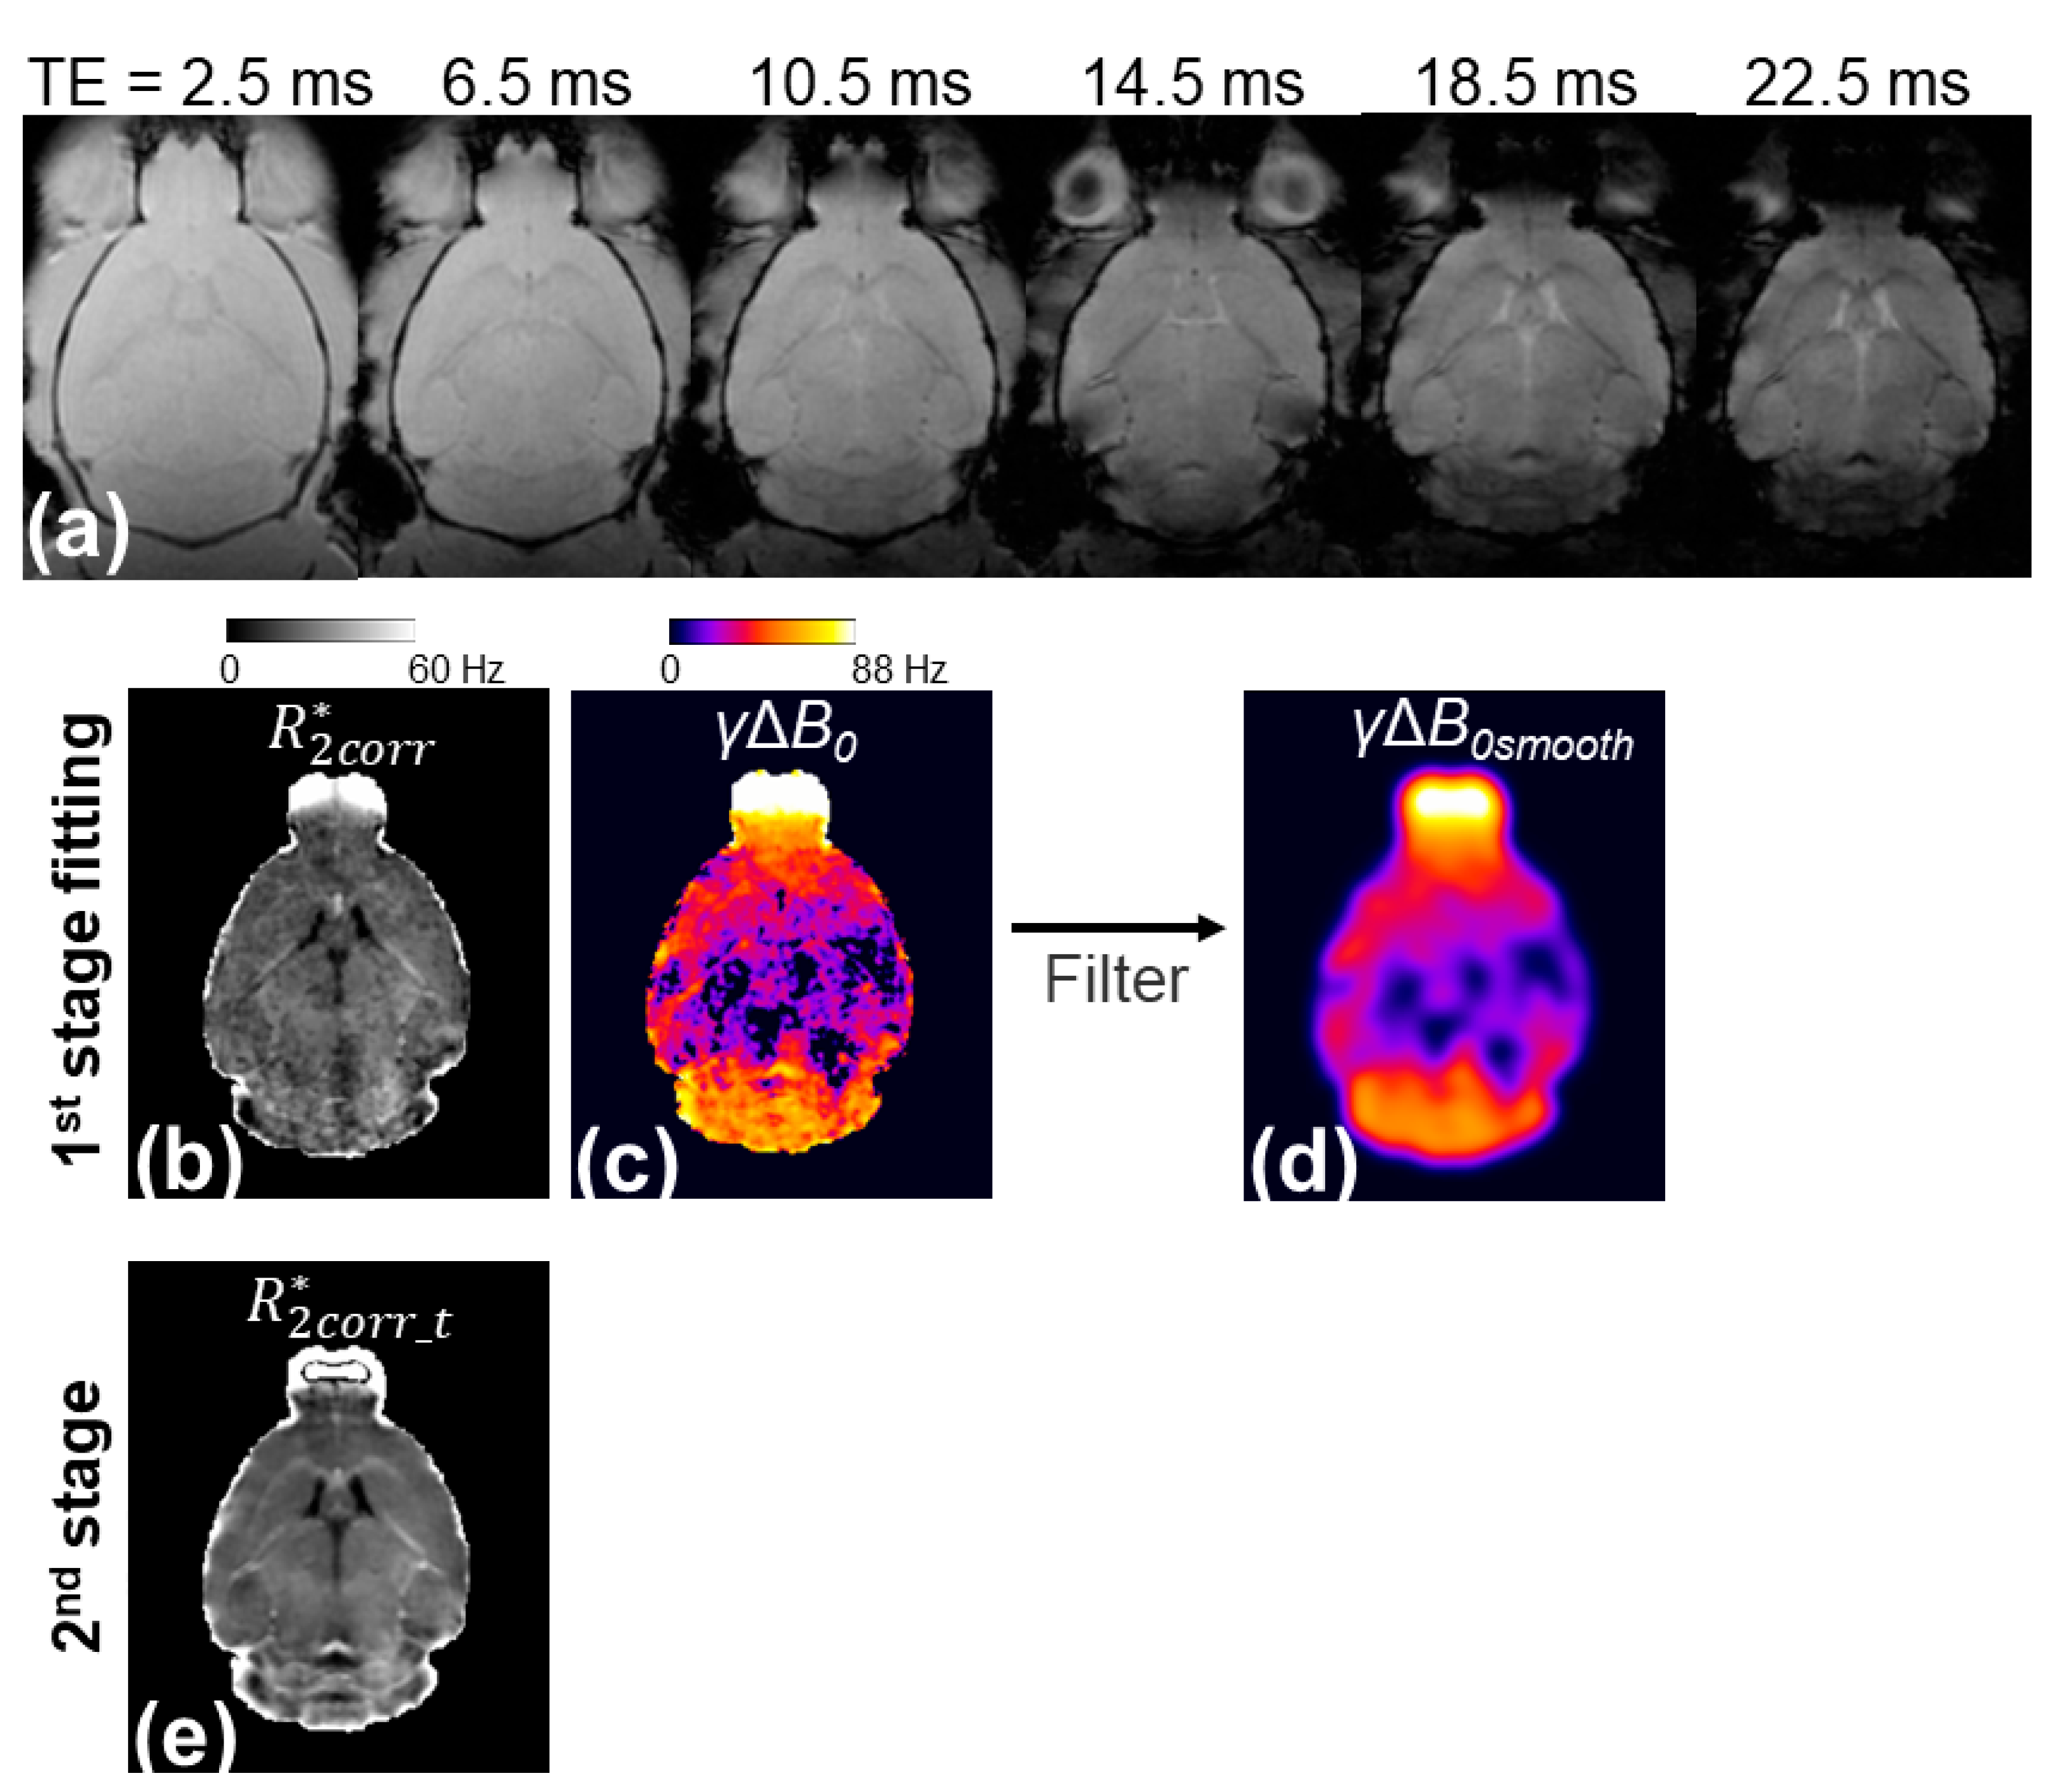

Figure 1 illustrates the workflow of the presented two-stage fitting procedure. The γΔB0 map generated by the three-parameter fit showed a large ΔB0 in regions with large magnetic susceptibility changes, such as the olfactory bulb, entorhinal cortex, and cerebellum, but it was noisy (Figure 1c). A smoothing kernel was applied to the γΔB0 map to reduce the noise effects while maintaining the spatial variation of ΔB0 (Figure 1d). The γΔB0smooth map was applied to the three-parameter model to remove the ΔB0 effect from the signal and reduce the unknown parameters from three to two, thereby generating a less noisy R 2 c o r r _ t * map (Figure 1e).

Figure 1. Illustration of the two-stage fitting procedure. In the first stage of fitting, the voxel-wise multi-echo GRE signals shown in (a) were fitted with the three-parameter model (Equation (1)) to generate corrected R 2 * ( R 2 c o r r * ) (b) and γΔB0 maps (c). Based on the assumption that the γΔB0 map is smooth on the x-y plane, a 2D Gaussian filter with a σgaussian of 390 µm was applied to the γΔB0 map to generate γΔB0smooth (d). In the second stage of fitting, the multi-echo GRE signals of each image voxel were divided by the s i n c ( γ B 0 s m o o t h T E / 2 )) and were then fit with the monoexponential model to generate the R 2 c o r r _ t * map with reduced sensitivity to noise (e).